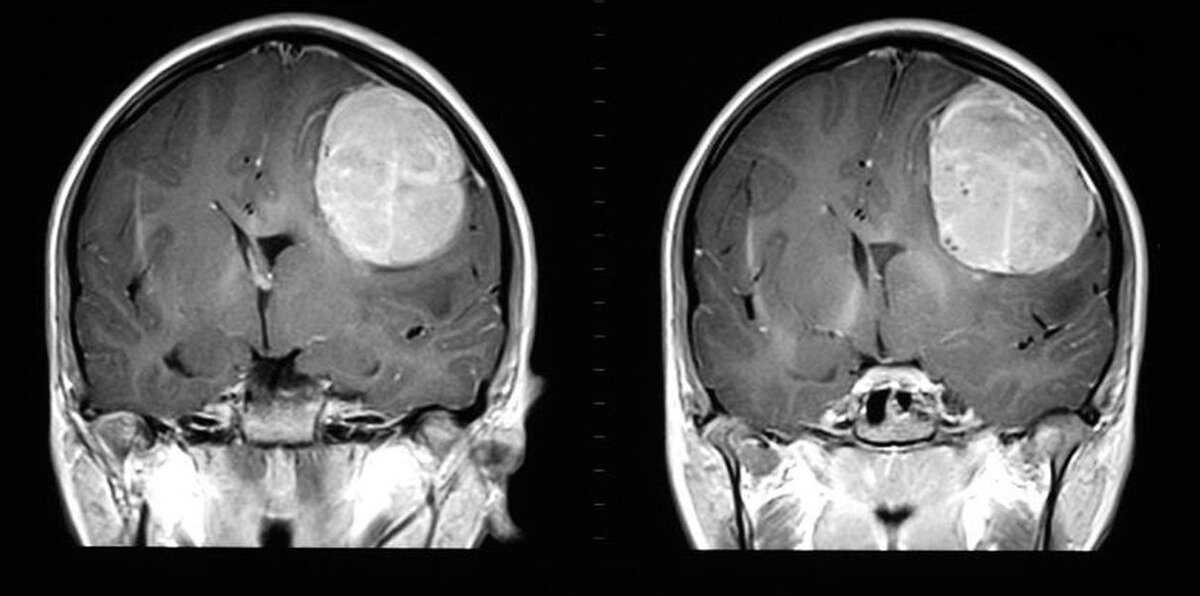

ОБЯЗАТЕЛЬНО К ПРОЧТЕНИЮ. ГЛАВНЫЕ СИМПТОМЫ РАКА МОЗГА

Рак головного мозга - серьезное заболевание, связанное с разрастанием злокачественной опухоли в головном мозге. Этот вид онкологии представляет огромную опасность по крайне мере тем, что длительный период имеет бессимптомный характер. Сама опухоль может образовываться из различных структур головного мозга. К ним относится как сама мозговая ткань - серое вещество, так и оболочки мозга, черепные нервы и их отростки, железистые образования, находящиеся в ЦНС. По статистике, из всех онкобольных, каждый 50-ый имеет рак мозга. Эффективность лечения во многом зависит от своевременности постановки диагноза. Для этого необходимо знать основные симптомы, сопровождающие болезнь.